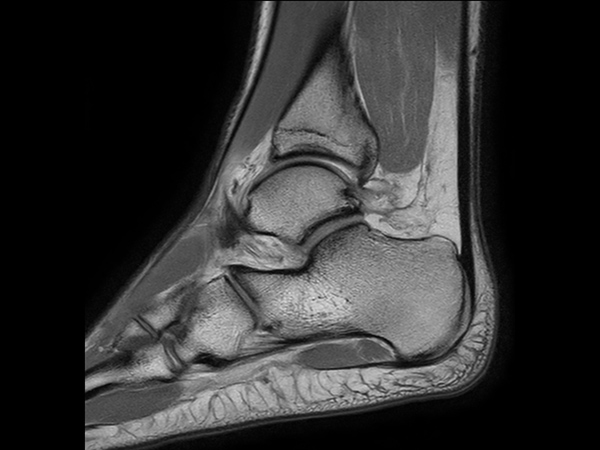

Sagittal T1w TSE

Sagittal 3D PDw SPAIR (0.6 mm, 7 min)

Sagittal 3D PDw SPAIR (0.5 mm, 7 min)

Sagittal 3D PDw SPAIR (0.5 mm, 5 min)